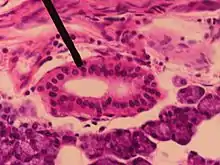

Histologie

Comme d'autres canaux excréteurs, le canal parotidien est formé de trois couches : muqueuse, musculeuse et adventicielle. La couche muqueuse est initialement formée d'un épithélium à double couche, dans lequel s'insère des cellules caliciformes. Peu avant son ouverture dans la cavité buccale, l'épithélium se transforme en un épithélium stratifié. La couche musculeuse est formée de fibres musculaires lisses, disposées longitudinalement. Ces fibres musculaires vont permettre le péristaltisme du canal mais disparaissent progressivement en se rapprochant du muscle buccinateur, mais on retrouve des fibres musculaires issues de ce muscle qui vont s'étendre sur le canal [5]. La couche adventicielle est composée d'un tissu lipofibreux richement vascularisé [6].